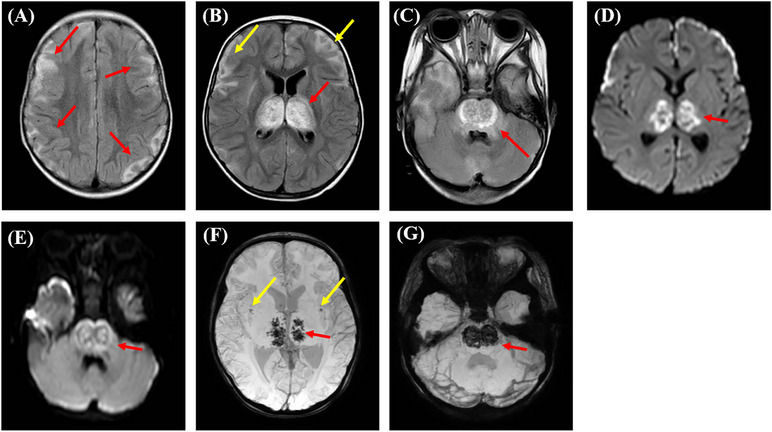

Case presentation: Here we report a 1-year-old girl with recurrent ITES and RANBP2 mutation. She was diagnosed with influenza-associated encephalopathy and made a full recovery on the first episode. After severe acute respiratory syndrome coronavirus 2 infection, the patient presented with seizures and deteriorating mental status. Brain magnetic resonance imaging revealed necrotic lesions in bilateral thalami and pons. Methylprednisolone, immunoglobulin, and interleukin 6 inhibitors were administered. Her consciousness level was improved at discharge. Nineteen cases of 2019 coronavirus disease-related ANE have been reported, of which 22.2% of patients died and 61.1% had neurologic disabilities. RANBP2 gene mutation was found in five patients, two of whom developed recurrent ITES.